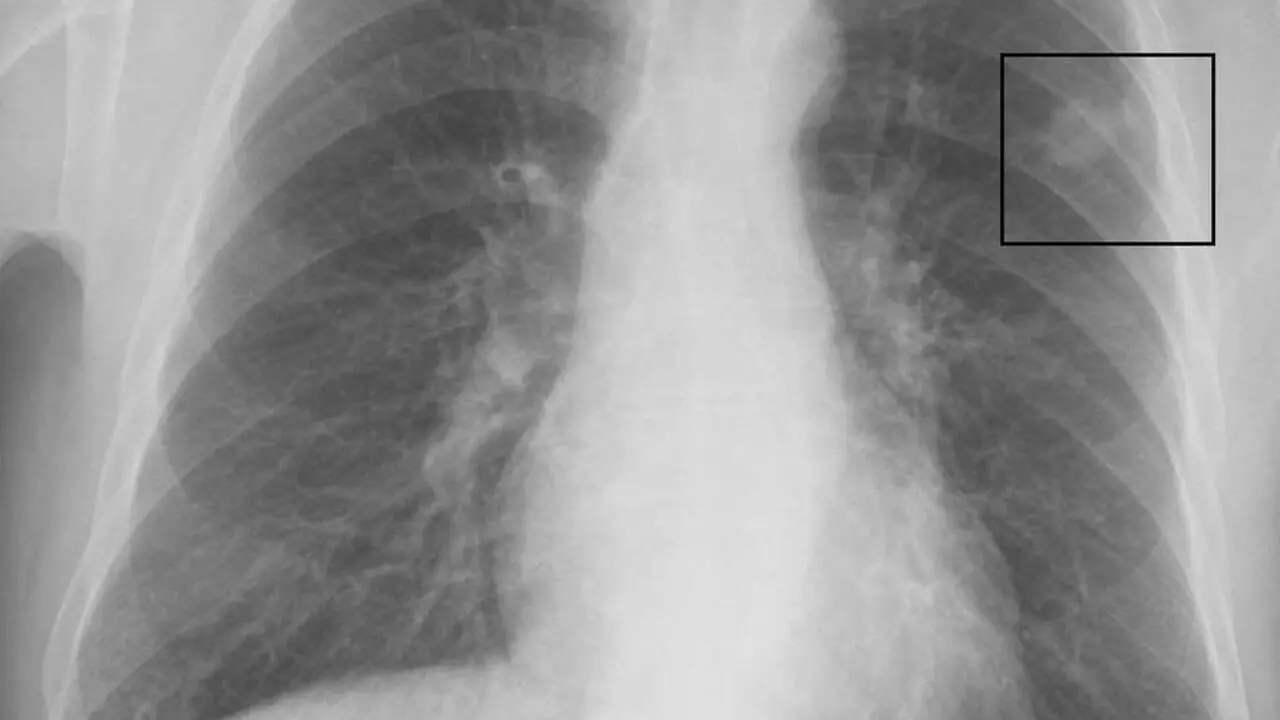

Modelo De Inteligencia Artificial Detecta E Localiza Em Segundos Achados Radiologicos Em Raio X De Pulmao Unicamp